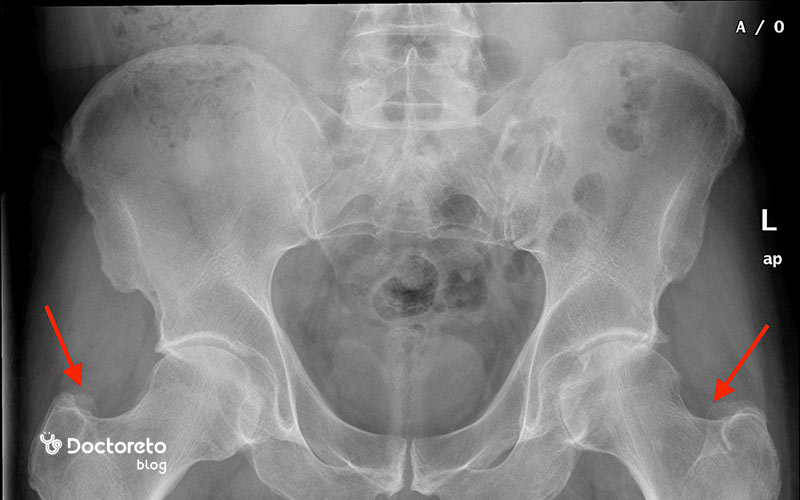

عکس پوکی استخوان لگن و ران

برای تشخیص و بررسی پوکی استخوان در لگن و ران، از روشهای مختلف تصویربرداری امآرآی، پزشکی هستهای و رادیوگرافی ساده استفاده میشود. در هر یک از این روشها، شاخصههای مختلفی ارزیابی میشوند. بهعنوانمثال MRI در پوکی استخوان اولیه جایگزینی پراکنده مغز استخوان با چربی را نشان میدهد؛ ادم و خطوط شکستگی بیشتر در شکستگیهای ثانویه دیده میشود.

خطوط شکستگیهای زیر غضروفی نیز در این تصاویر مشخص است. تصاویر MRI در افراد مبتلا به پوکی استخوان، تصویر واضحی از بافت نرم اطراف لگن، مانند ماهیچهها و تاندونها را نیز ارائه میدهد.